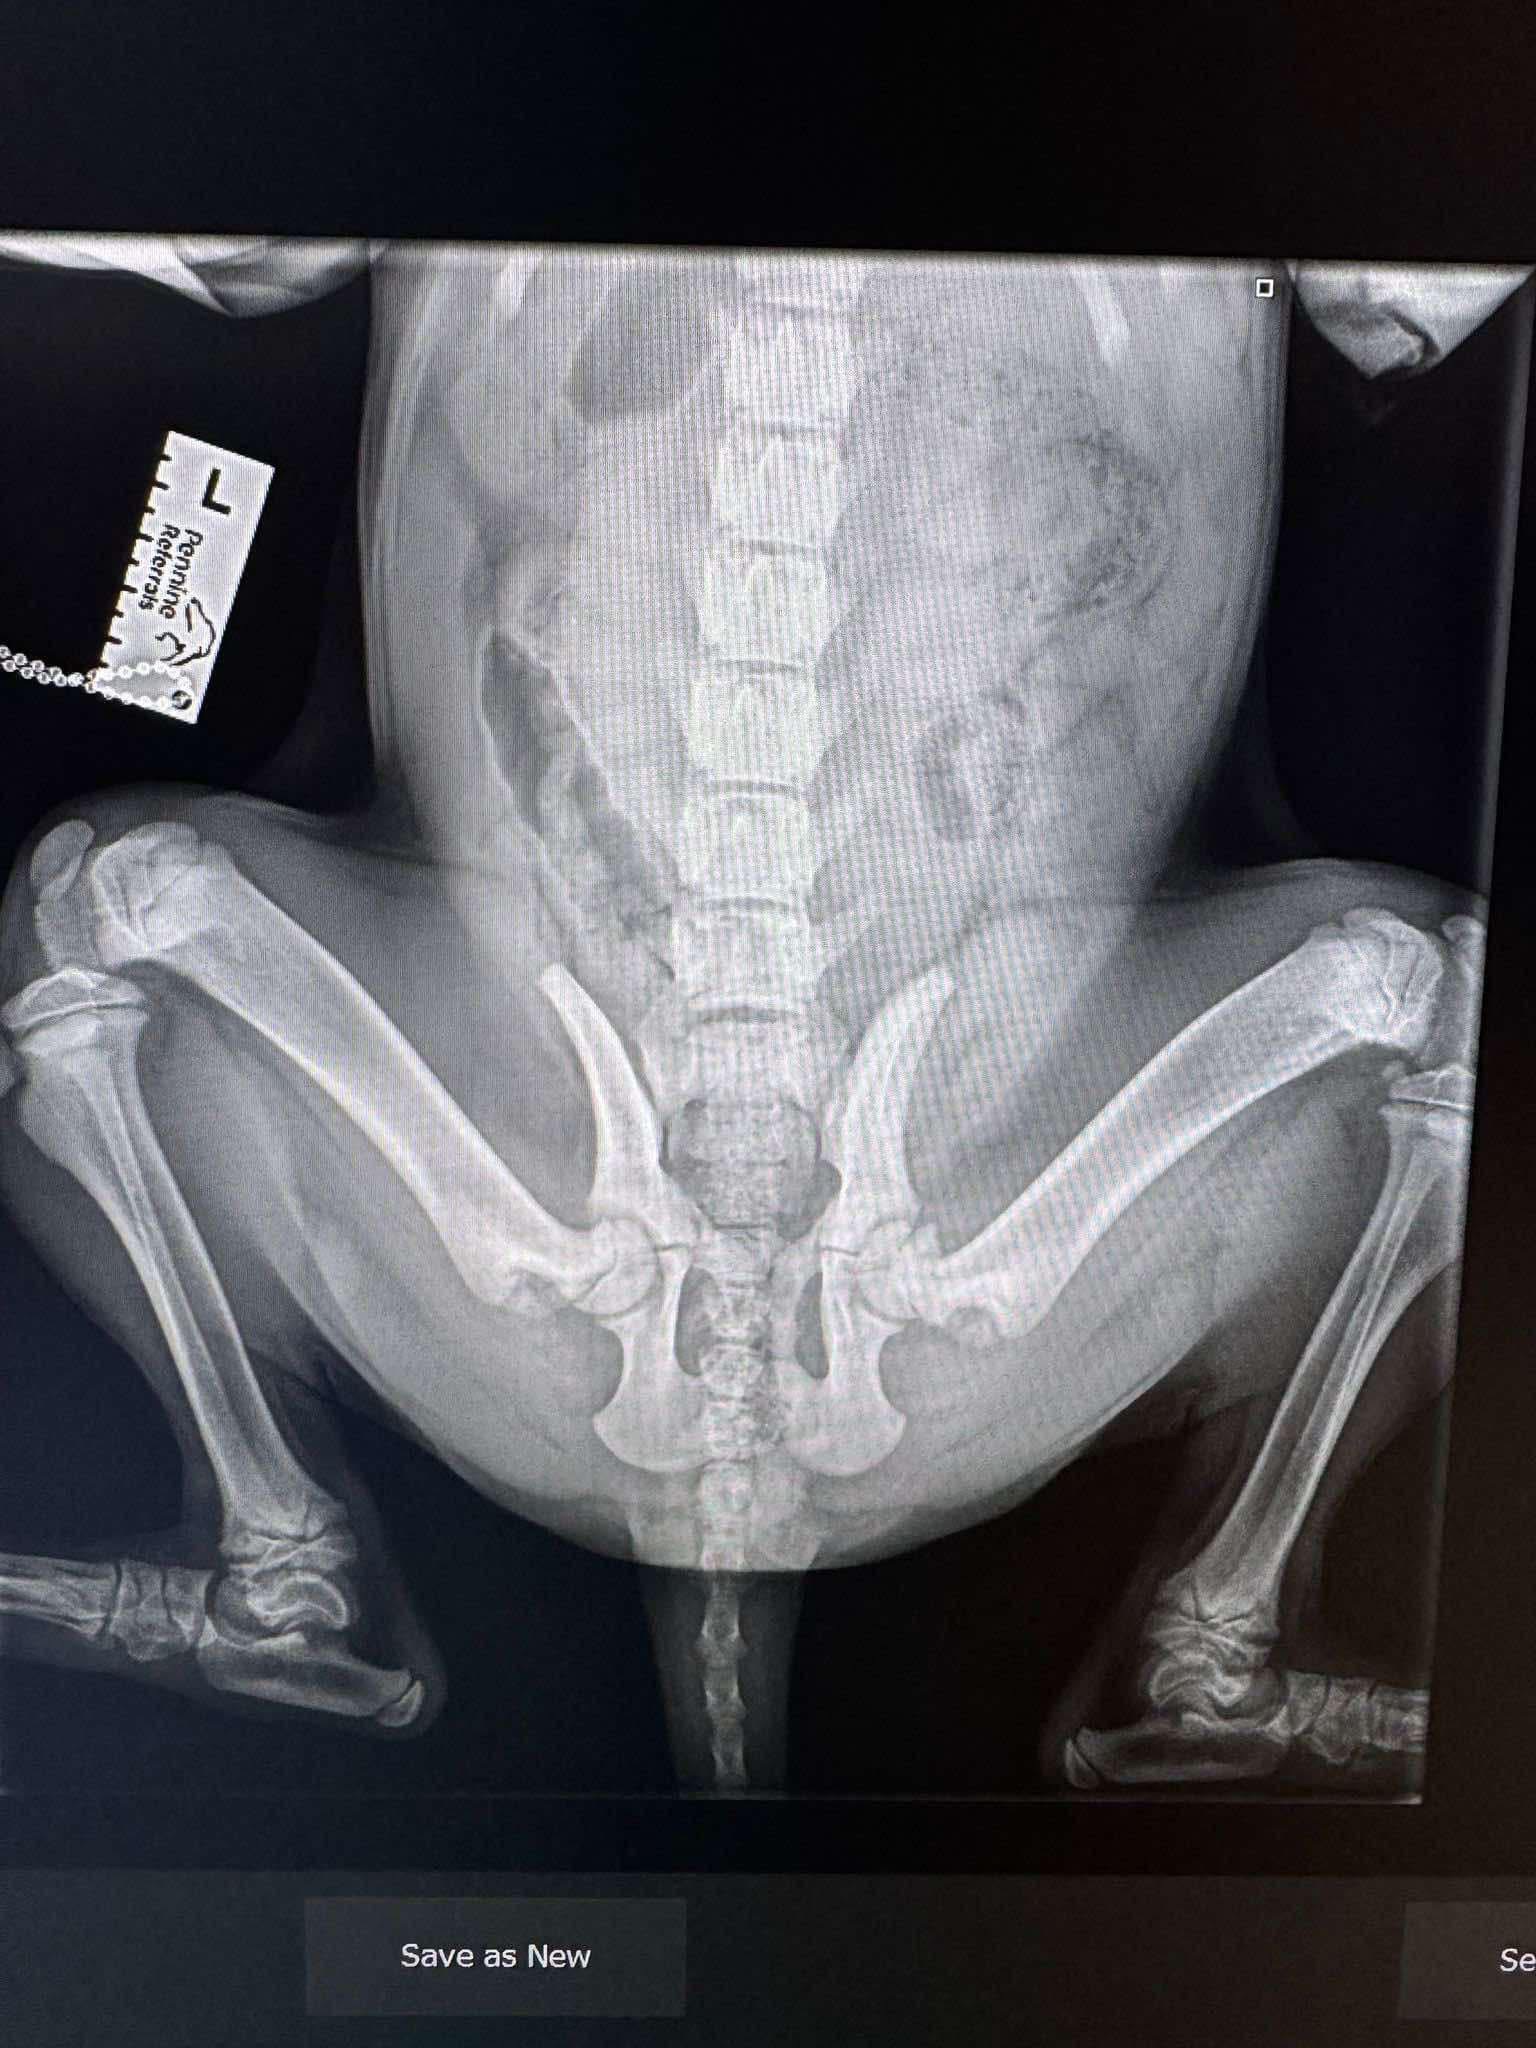

🔹 INJURIES TO LIL REDD

- 9 broken ribs close to her spine

- Possible hip damage